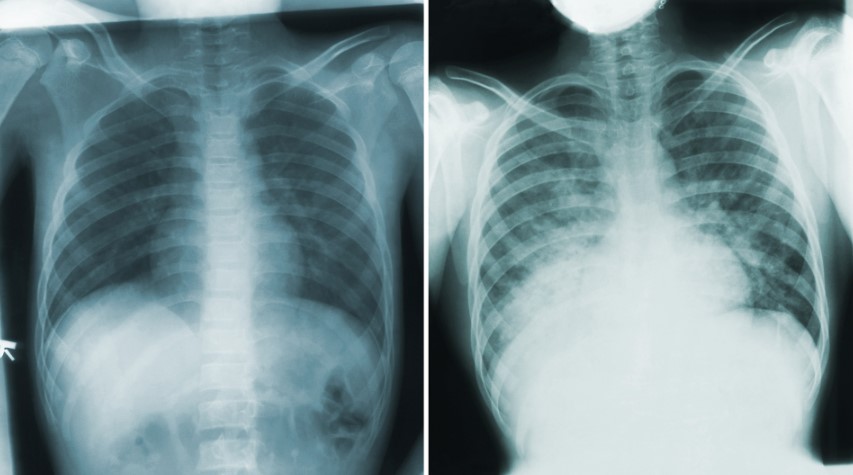

Según el Centro para el Control y la Prevención de Enfermedades (CDC), la peste neumónica presenta un rápido período de incubación, de tan solo un día, y se manifiesta con síntomas graves como fiebre alta, dolor de cabeza, debilidad, neumonía con dificultad para respirar, dolor en el pecho y tos, que en ocasiones incluye mucosidad con sangre o acuosa.